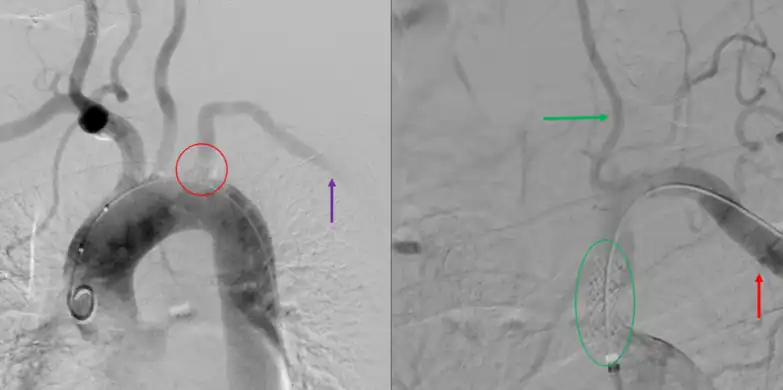

CT angiography of subclavian steal phenomenon

Angiogram of subclavian steal phenomenon before and after stent placement